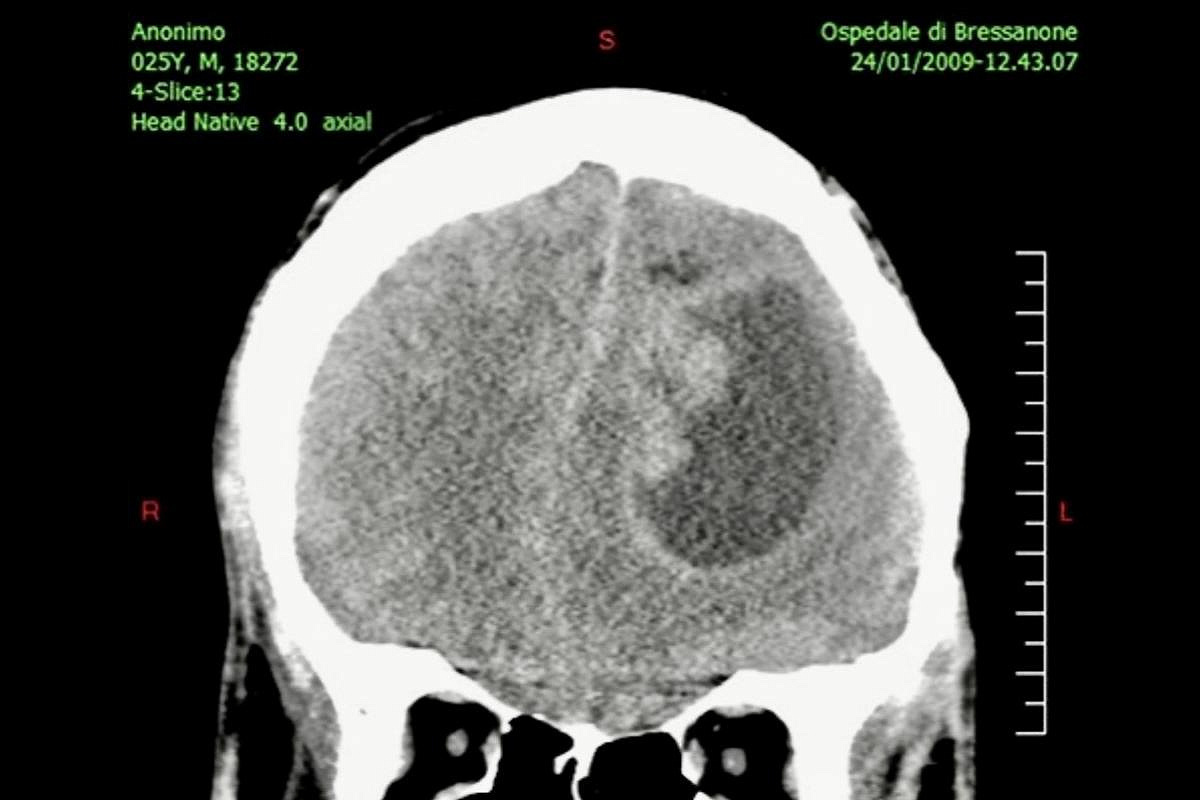

Израильские учёные предлагают новый подход к лечению рака мозга Команда израильских исследователей представила экспериментальный метод лечения опухолей мозга, который помогает лекарствам проходить через гематоэнцефалический барьер — естественную «броню» нашего мозга.

Если подход подтвердит эффективность, у врачей появится новый инструмент против одной из самых опасных и плохо поддающихся терапии форм рака.

Опухоли мозга остаются одной из самых сложных областей онкологии. Даже когда врачи знают, какие препараты способны замедлить рост раковых клеток,

их действие ограничено: мозг защищён плотной сетью капилляров, которые не пропускают большую часть веществ. Этот механизм спасает нас от токсинов

и инфекций, но одновременно делает опухоли практически недоступными для лечения.